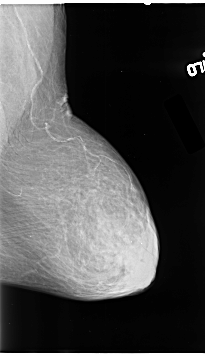

B_3130_1.LEFT_MLO

LEFT_MLO LINES 4624 PIXELS_PER_LINE 2664 BITS_PER_PIXEL 12 RESOLUTION 50 NON_OVERLAY